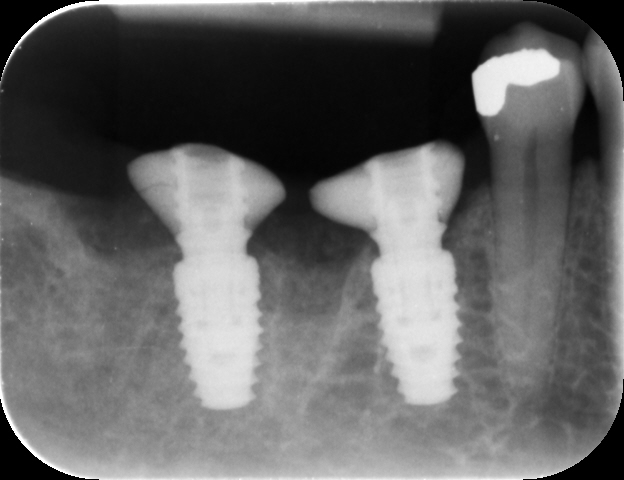

The implants (5 × 9 mm CONELOG PROGRESSIVE-LINE, BioHorizons Camlog) were then placed using the sleeveless surgical guide and the CONELOG guided kit (Figs. 9 & 10).

After verification of the implant placement, the grafting material (MinerOss Putty allograft, BioHorizons Camlog) was packed into the site to the bone level to reduce the build-up of grafting material in the soft tissue.

Fig. 9: Implants placed using a surgical guide to ensure precision.

Fig. 10: Implants in place, situation after grafting.

Fig. 12: Post-op radiograph.

After a healing period of three months, the Medit i700 intra-oral scanner was used to record the implant position and soft-tissue profile, ensuring optimal prosthetic planning and precise restoration (Fig. 12). The implant crowns were constructed using custom milled titanium abutments with a zirconia crown. Care was taken to ensure that any zirconia in contact with the tissue was polished rather than glazed to promote optimal soft-tissue health.